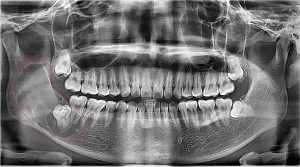

Nhổ răng khôn hay răng số 8 là một quá trình thực hiện bóc tách bác mô nướu, dùng dao chuyên dụng thực hiện mở xương hàm để lấy răng khôn hoặc nhổ nhiều chiếc răng khôn của bạn.

Răng khôn bị nhiễm trùng